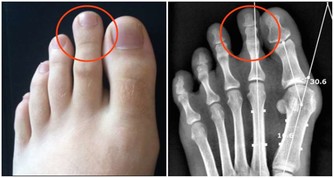

口腔潰瘍的情況下密切接吻有可能感染艾滋病。

艾滋病的傳染要滿足三個條件:傳染源,傳播途徑,易感人群。

即使會傳染,但實際上有很多前提條件:

1.一方確實感染了艾滋病毒;

2.感染者沒有經過任何抗病毒治療;

3.口腔有潰瘍出血。

口腔潰瘍接吻,會不會被感染艾滋? 醫生透露:一種情況真的有可能

即使三個條件都滿足,少量艾滋病毒進入身體,病毒量也通常達不到染病的程度。而且,人體自身的免疫功能,面對艾滋病毒也會啟動防護機制。

因此,口腔潰瘍出血在概率上的確存在感染的可能,但被感染的機率微乎其微。

至於很多人擔心,有口腔潰瘍的情況下接吻感染,就​​算真的發生,也是因為血液暴露,歸於血液傳播,而不能說接吻是艾滋病的一個傳播途徑。